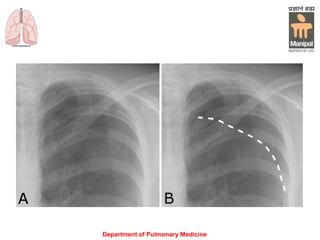

• Chest X-ray shows the sharply defined

edge of the deflated lung with complete

translucency (no lung markings) between

this and the chest wall